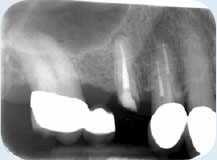

Een 72-jarige dame meldt zich op verzoek van haar tandarts voor een specifiek consult. Zij heeft in de bovenkaak twee problemen:

De brug in het eerste kwadrant heeft een probleem aan de voorste pijler: de kroon op de 15 zit los en lekt (afbeelding 1 - 3 ). De verwijzend tandarts vraagt om advies.

OPT